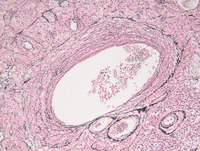

Reticulin stain

Perivascular reticulin condensation around clusters of tumor cells